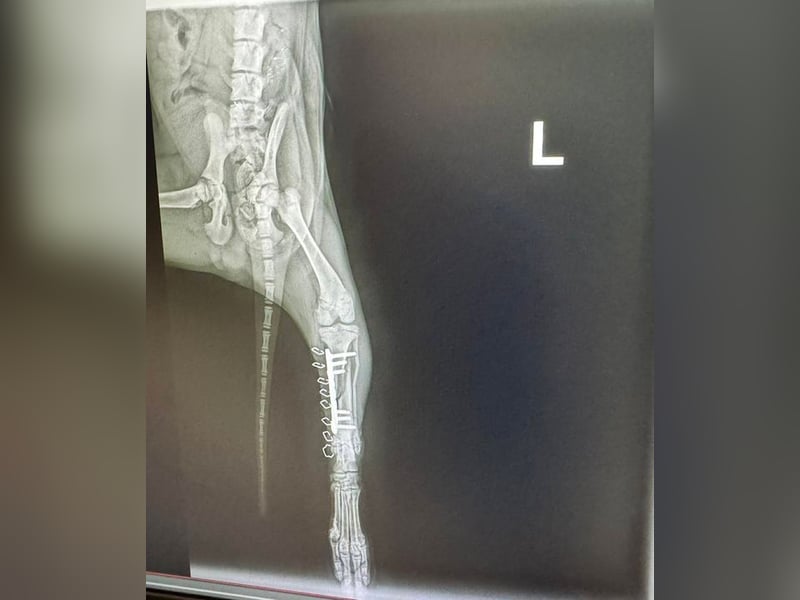

Bemerkungen: Hubsi wurde von einem Auto angefahren. Er hatte ein gebrochenes Hinterbenchen. Dieses wurde erfolgreich operiert.

Hubsi ist ein sehr lebhafter und verspielter Welpe und seit Mitte März 2026 in unserem Partnertierheim. Er kam zu diesem Zeitpunkt direkt aus der Tierklinik, denn er wurde in der Nähe einer Romasledlung von einem Auto angefahren und erlitt einen Bruch des Hinterbeinchens. Er wurde natürlich operiert und erholt sich momentan bei der Tierheimleitung im Wohnhaus.